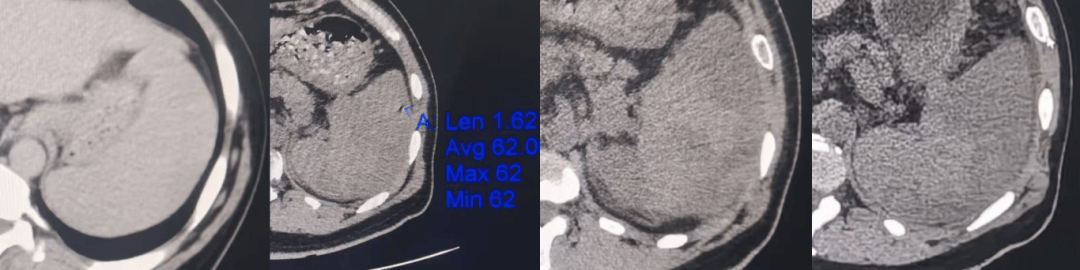

随后,术后的抗炎水化治疗有序进行。田先生的血小板更是从术前的9×109/L,到术后第10天升至100×109/L,乏力、腹胀等不适感消失。

△入院至出院CT监测无并发症、脾形态恢复